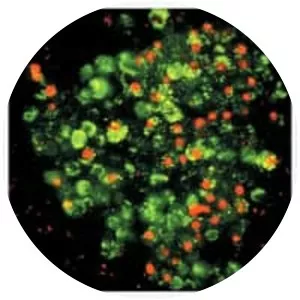

Bromodeoxyuridine photograph

Bromodeoxyuridine is a synthetic nucleoside that is an analog of thymidine. BrdU is commonly used in the detection of proliferating cells in living tissues. 5-Bromodeoxycytidine is deaminated to form BrdU.